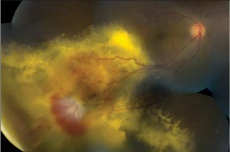

Retinal capillary hemangioma with prominent retinal feeder vessels[26] |